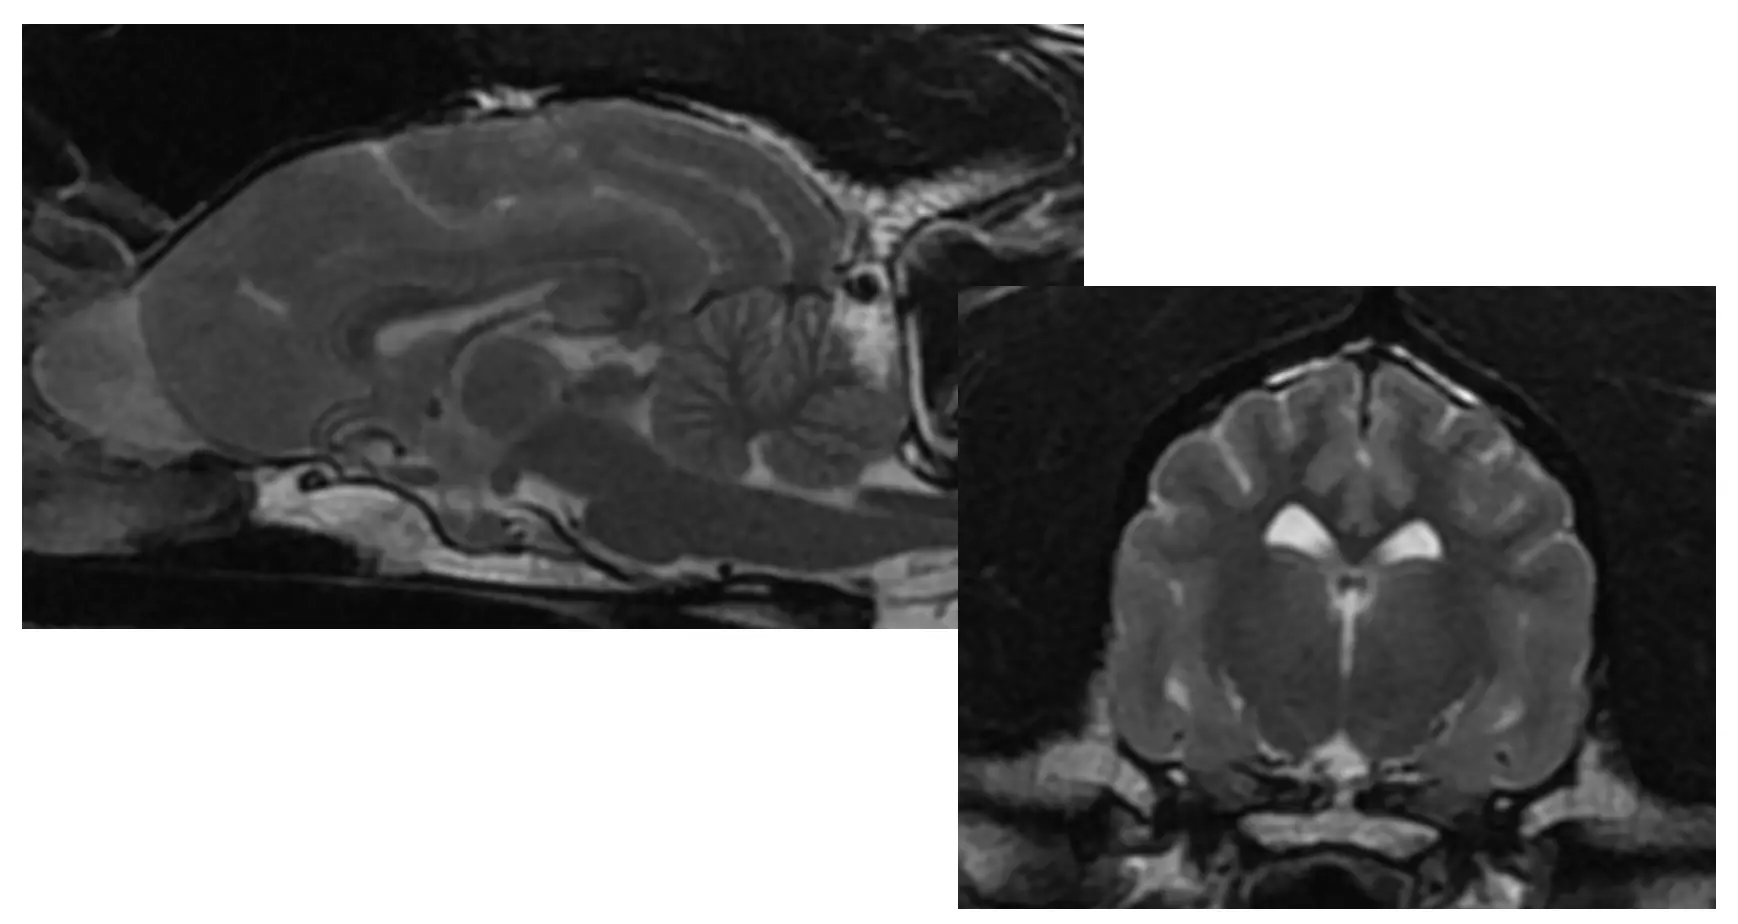

- In both human and veterinary neurology, magnetic resonance imaging (MRI) is the gold standard imaging modality.

- Neurologists use MRI to view the patient’s nervous system (brain, spinal cord, and peripheral nerves). This amazing soft tissue detail gives a better understanding of a patient’s nervous system, why the patient may be having neurological signs, and allows the neurologist to make the most appropriate treatment and testing recommendations.